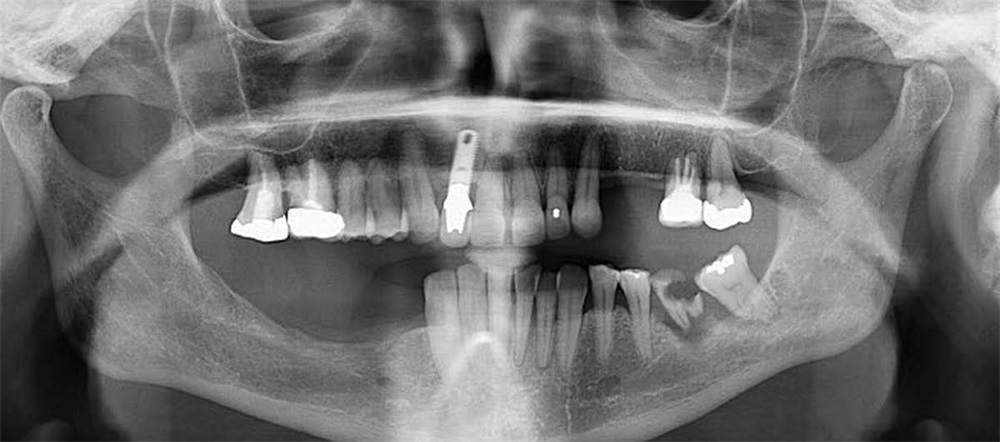

Our patient, a healthy woman in her early 60s, presented with a terminal dentition (Fig. 1) in both arches, collapsed bite, unstable occlusion, midline shift, asymmetric horizontal plane and bone loss (Fig. 2). She was looking for a fixed solution that would give her the confidence to smile, eat and socialize without restrictions. Several previous treatment plans suggested placing provisional dentures as an interim until the implant stabilized, which did not resonate with her desires during the healing phase.

Today, two years after final delivery, the patient remains stable with no mobility, inflammation or prosthetic complications. There is excellent soft tissue health around the implants. Full function was restored and the patient enjoys all foods without restrictions. Radiographs show stable bone levels around all implants, including the pterygoid site (Fig. 18).

Fig. 18